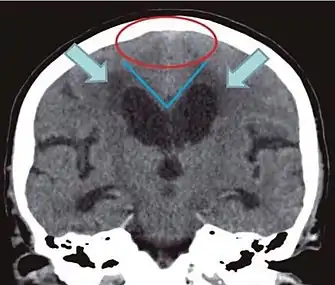

- Imaging from magnetic resonance imaging (MRI) or computed tomography (CT) is needed to demonstrate enlarged ventricles and no macroscopic obstruction to cerebrospinal fluid flow. Imaging should show an enlargement to at least one of the temporal horns of lateral ventricles, and impingement against the falx cerebri resulting in a callosal angle ≤ 90° on the coronal view, showing evidence of altered brain water content, or normal active flow (which is referred to as "flow void") at the cerebral aqueduct and fourth ventricle.

| Normal pressure hydrocephalus | Brain atrophy | |

| Preferable projection | Coronal plane at the level of the posterior commissure of the brain. | |

| Modality in this example | CT | MRI |

| CSF spaces over the convexity near the vertex (red ellipse | Narrowed convexity ("tight convexity") as well as medial cisterns | Widened vertex (red arrow) and medial cisterns (green arrow) |

| Callosal angle (blue V) | Acute angle | Obtuse angle |

| Most likely cause of leucoaraiosis (periventricular signal alterations, blue arrows |

Transependymal cerebrospinal fluid diapedesis | Vascular encephalopathy, in this case suggested by unilateral occurrence |

MRI scans are the preferred imaging. The distinction between normal and enlarged ventricular size by cerebral atrophy is difficult to ascertain. Up to 80% of cases are unrecognized and untreated due to difficulty of diagnosis.[9] Imaging should also reveal the absence of any cerebral mass lesions or any signs of obstructions. Although all patients with NPH have enlarged ventricles, not all elderly patients with enlarged ventricles have primary NPH. Cerebral atrophy can cause enlarged ventricles, as well, and is referred to as hydrocephalus ex vacuo.